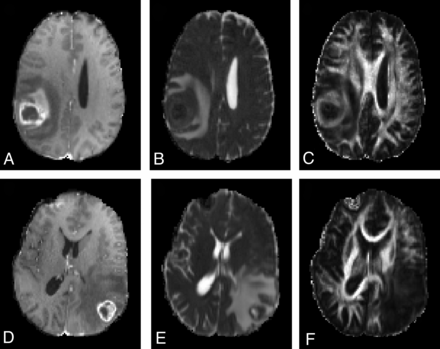

Representative MR images of patients with glioblastoma and metastasis are shown in Fig 1. The MD maps in both cases showed similar levels of restricted diffusion in the enhancing parts. In contrast, the FA maps showed that the glioblastoma had higher FA than the brain metastasis. The high FA rim extended to the immediate peritumoral regions in glioblastomas. Similar observation was made with most cases as summarized by the boxplots shown in Fig 2A, -B. The median FA value of glioblastomas from the ER and IPR was significantly higher than that of brain metastases (P < .01). There was no significant difference in the median values of MD from all the regions. None of the parameters showed significant differences from the distant peritumoral regions.

Comparison of imaging features between glioblastomas (A–C) and brain metastases (D–F). Both show ring enhancement and extensive edema on axial contrast-enhanced T1-weighted images (A and D) and restricted diffusion of the enhancing part on MD maps (B and E). However, for the FA map, the glioblastoma case demonstrates high FA values from the enhancing region. The high FA starts from the enhancing region and extends to the immediate peritumoral region, making an FA rim.